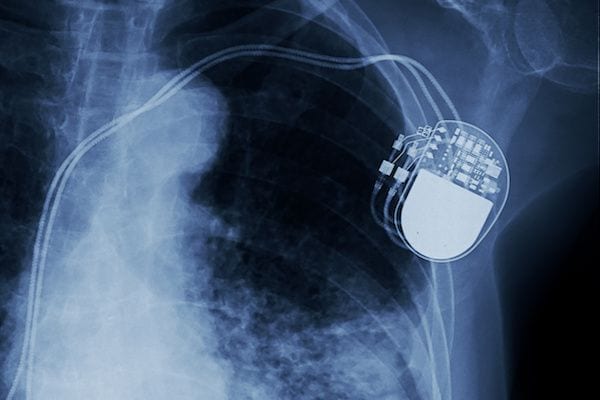

El implante de marcapasos definitivo consiste en colocar un dispositivo electrónico de forma quirúrgica bajo la piel, generalmente debajo del hombro izquierdo y la clavícula.

Está compuesto por un generador de impulsos eléctricos, contiene una batería y uno o dos electrodos, según sea el caso, que se introducen por las arterias hasta llegar al corazón.

Para implantar un marcapasos definitivo se debe preparar al paciente para una intervención. Generalmente se aplica anestesia local; el proceso quirúrgico podría durar una hora aproximadamente, para ser internado un solo día. Se aplica anestesia local en el sitio donde va a implantarse el marcapasos, generalmente en el pecho debajo de la clavícula izquierda. Se introducen los electrodos por una vena, estos son guiados y se llevan de forma segura, a través de control radioscópico, hasta el corazón. Se hacen las pruebas hasta determinar cuál es el mejor sitio para ubicar los electrodos y luego se fijan. Seguidamente se unen los electrodos al marcapasos, se comprueba el correcto funcionamiento del aparato, se implanta y se cierra la herida con puntos de sutura.